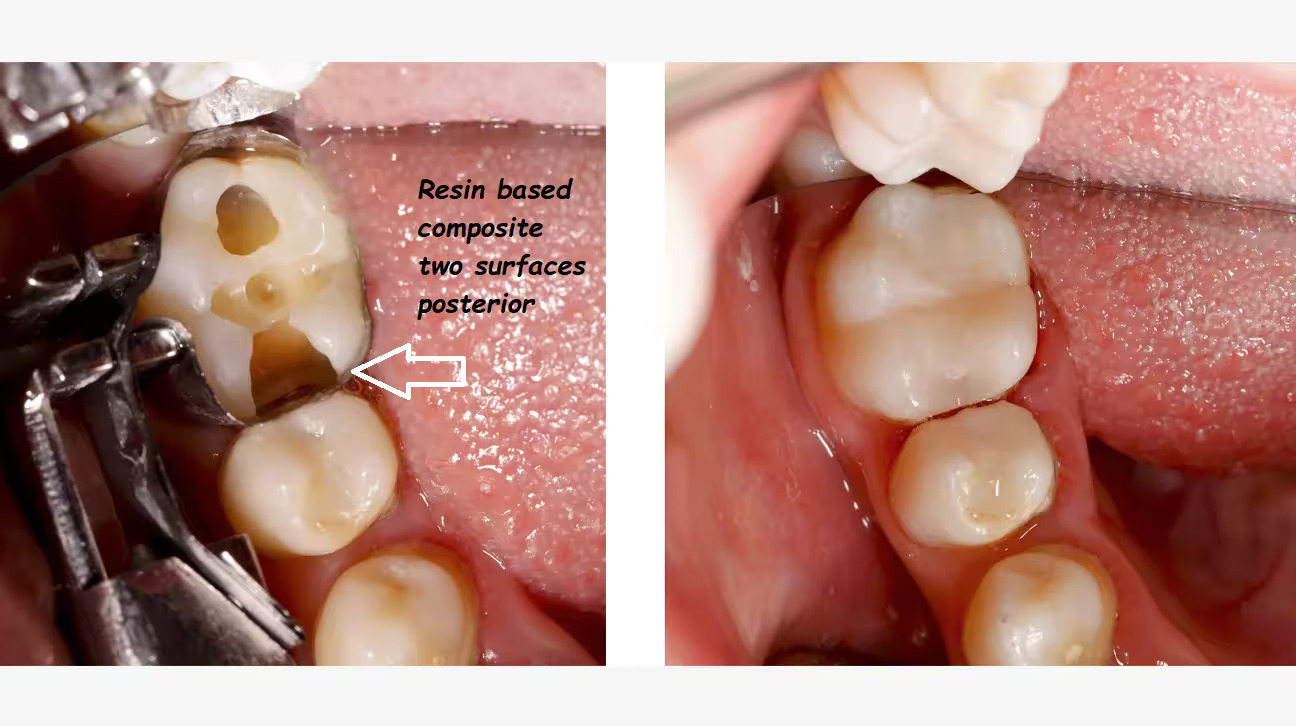

We repair decayed or damaged teeth using tooth-colored fillings that blend seamlessly with your smile.

Anterior restorations focus on front teeth for a natural look, while posterior restorations strengthen back teeth to restore chewing function.

These treatments are durable, aesthetic, and preserve your natural tooth structure.